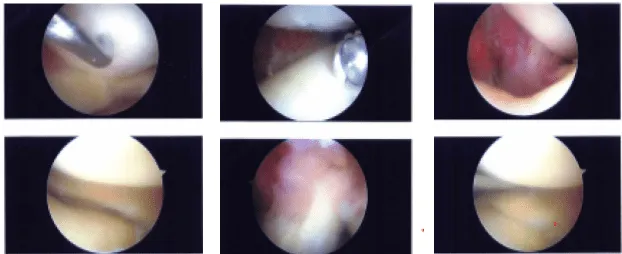

Se realizó un portal anterior lateral e insertó el artroscopio. Se realizó una porta anterior medial utilizando una aguja espinal. El examen del compartimento tibial medial mostró una ruptura del radio de la parte posterior del cuerpo posterior del menisco medial.

La resección de los márgenes del desgarro se realizó mediante biters y afeitadoras, lo que logró márgenes equilibrados. También había un desgarro horizontal que fue desbordado. Se lograrían márgenes equilibrados. Había osteoartritis de grado III a grado IV del cóndilo femoral medial.

El examen de la muesca infrapatelara mostró un LCA intacto. El examen del compartimento femoral lateral mostró menisco y cartílago intactos del compartimento tibiofemoral lateral.

El examen del compartimento patelofemoral mostró un desgarro de grado I a grado II del cartílago de la rótula, que fue desbridado con el uso de una afeitadora. La rodilla estaba completamente irrigada. Se tomaron y guardaron las fotos finales.

Imágenes intraoperatorias